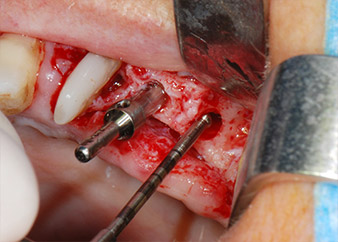

Avant la pose de l'implant, les tissus infectés ont été retirés de l'os alvéolaire sur le site de l'implant et autour des dents piliers à l'aide d'un insert initialement conçu pour le façonnage de l'os et la récupération des copeaux d'os (Piezomed, insert B5) (Figures 6 et 7).

Les lits implantaires ont été préparés sur les sites 25 et 26 à l'aide d'instruments rotatifs, utilisés dans un contre-angle avec un rapport de transmission 20:1 avec un nouveau moteur d'implantologie puissant (Implantmed, W&H) (Fig. 8).

La préparation finale près du sinus a encore une fois été réalisée à l'aide d'un instrument piézoélectrique (Piezomed, insert S2).